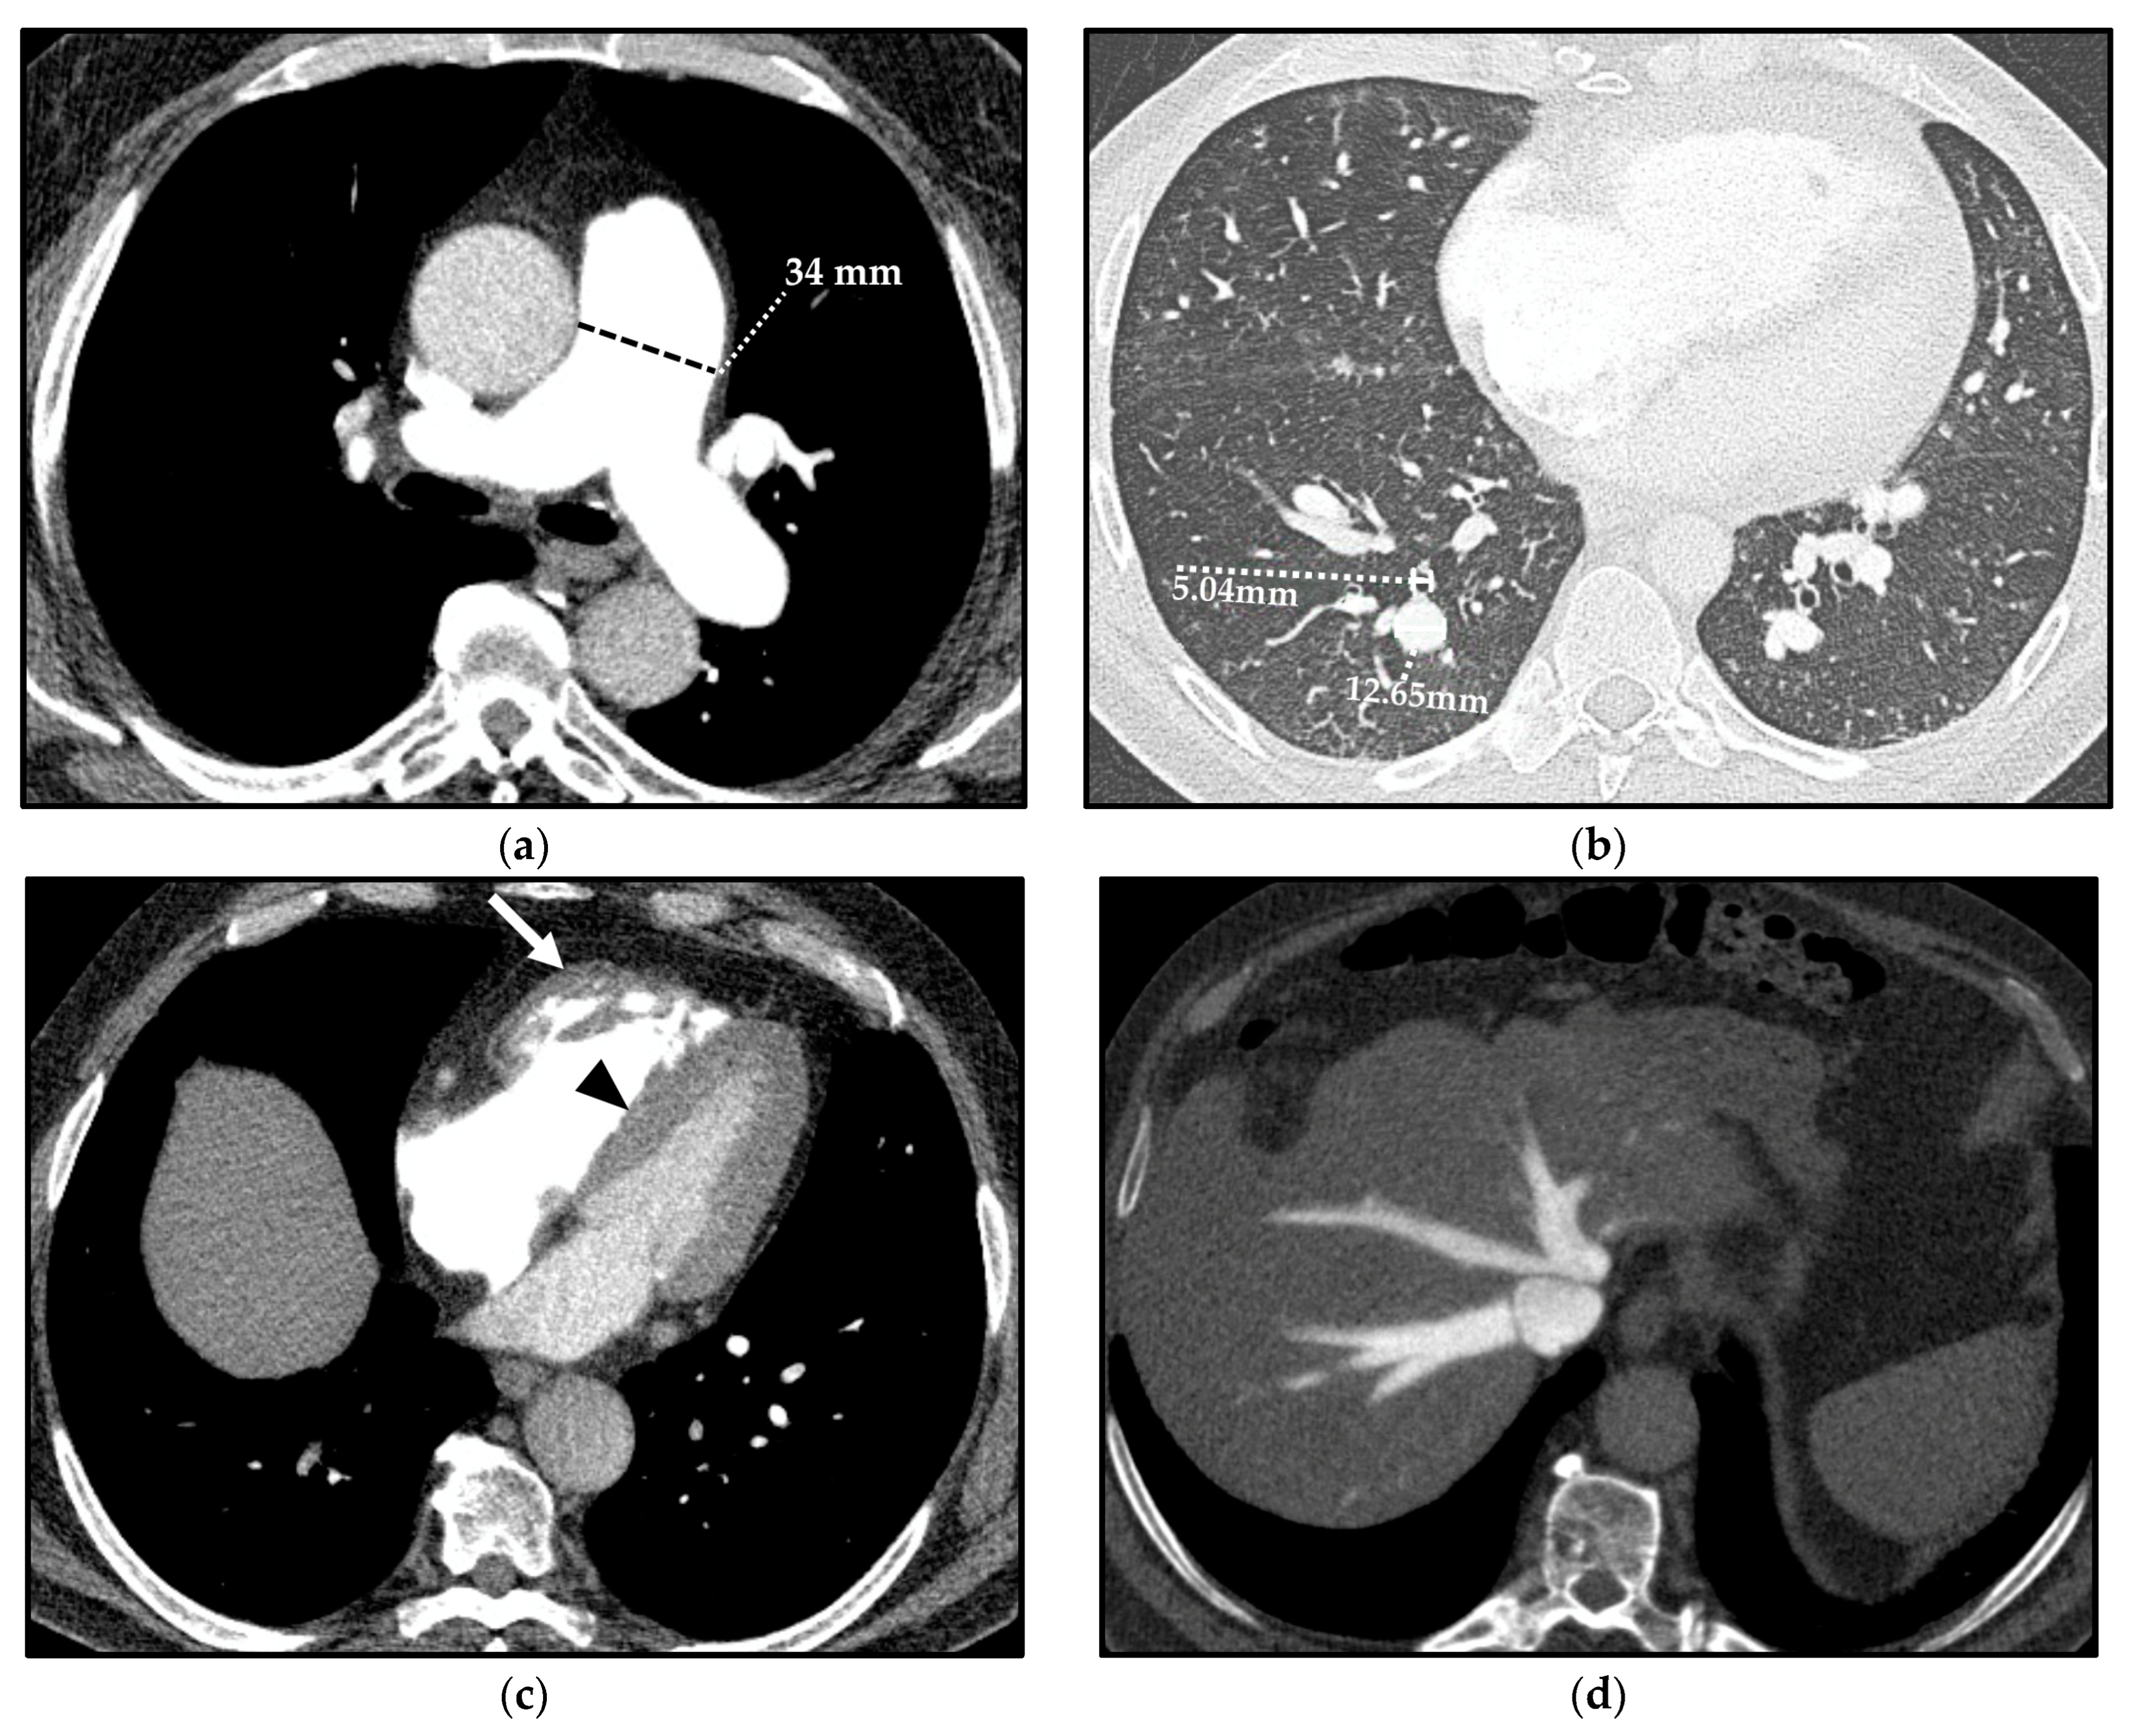

In patients with PH, the increase in PAP results in structural and hemodynamic changes that cause indirect vascular and cardiac CT signs, which should be recognized by radiologists (Figure 4).

Computed tomography (CT) indirect signs of pulmonary hypertension (PH). Vascular CT signs: main pulmonary artery (MPA) dilation (34 mm) (a) and increased segmental artery-to-bronchus ratio (>1) (b). Cardiac CT signs: right ventricle (RV) hypertrophy, with free wall thickness > 4 mm and trabecular hypertrophy (arrow), and flattening of the ventricular septum (arrowhead) (c). Extensive reflux of contrast medium into the inferior vena cava and hepatic veins (d).

The vascular CT signs of PH reflect the underlying mural architecture of the vessels [16,17]. The multiple parallel elastic laminae that compose the wall of central pulmonary arteries (PAs) allow the caliber adaptation of main, lobar, and proximal segmental arteries to vascular bed resistance. On the other hand, a prevalent muscular component characterizes the distal segmental and subsegmental arteries, which are highly responsive to circulating factors and local stresses and are the most involved vessels in PH. Hypoxic vasoconstriction, vascular remodeling, and proliferative vaso-occlusive lesions usually occur at this distal level [16,17]. This is the reason why the earliest appreciable CT sign related to PH is the dilation of the proximal PAs and the sudden caliber decrease in peripheral ones [18].

A mean diameter of the main PA (MPA)—also known as the pulmonary trunk—(measured at its largest point within 3 cm of its bifurcation) ≥29 mm is predictive of PH with a sensitivity, specificity, and positive predictive value (PPV) of 87%, 89%, and 97%, respectively [19]; specificity increases up to 100% when the dilation of the MPA is matched with a segmental artery-to-bronchus ratio > 1 in 3 out of 5 pulmonary lobes on axial CT scans [19,20].

Cardiac CT signs of PH depend on the exceeding adaptative mechanisms and subsequent failure of the RV.

Prolonged and severe PH ultimately impacts on the RV, and this is manifested as hypertrophy followed by dilation of the ventricular cavity and straightening of the interventricular septum, causing an abnormal septal movement that finally injures the left ventricle (LV) function [25]. On CT, an RV free wall thickness > 4 mm is used to define “hypertrophy” [26]. A CT sign of RV dilation, on axial images, is characterized by an RV diameter greater than that of LV up to LV compression in severe cases [27]. Straightening or bowing of the interventricular septum yields a sensitivity and specificity of 86% and 91%, respectively, for PH identification, usually evident when the RV pressure is >30 mmHg [28].

Reflux of contrast into the inferior vena cava and hepatic veins on first-pass contrast-enhanced CT (e.g., CTPA) is a specific and indirect sign of right heart dysfunction [29].